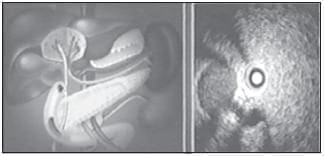

La ecoendoscopia biliopancreática es una de las principales aplicaciones de este examen. Usualmente, la exploración se realiza de forma retrógrada: el transductor se coloca en la tercera porción del duodeno y después se retira de forma progresiva. Si la exploración es completa, la visualización del páncreas y la vía biliar extrahepática es posible, prácticamente, en el 100% de los pacientes (23). Además, la exploración de los grandes vasos adyacentes al páncreas es posible también de forma casi constante. La proximidad de la sonda de ultrasonido al área biliopancreática (figura 12) permite utilizar sondas de frecuencia elevada (7,5 y 12 mHz), con lo que se consigue una excelente definición de esta área. De esta forma, es posible visualizar lesiones parenquimatosas de diámetro inferior a 10 mm (24). Por el contrario, hay limitaciones en la profundidad de campo, por lo que la exploración de la región del hilio hepático sólo es posible en una cuarta parte de los casos.

FIGURA 12. Obsérvese cómo el transductor de eco se puede colocar muy cerca de la región biliopancreática. En este caso se pueden ver la vena porta, el conducto de Wirsung y el colédoco.